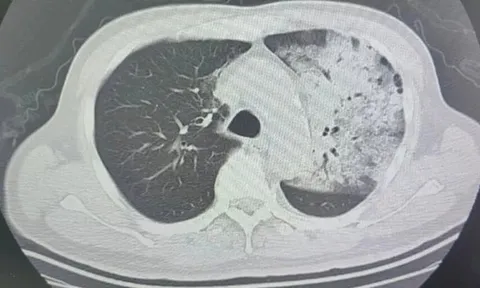

Người đàn ông sốt 40 độ C, phổi gần như 'trắng xóa", chỉ vài ngày đã suy đa tạng: Thủ phạm liên quan đến thói quen nhiều gia đình vẫn mắc

Một chiếc điều hòa lâu ngày không được vệ sinh có thể tiềm ẩn rủi ro sức khỏe nghiêm trọng mà nhiều người không ngờ tới.